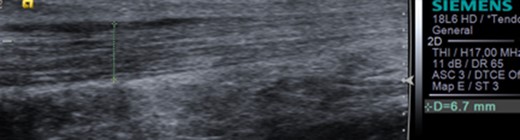

Dynamic ultrasound examination of the left heel showed a diffusely thickened subcutaneous bursa, with fluid-rich islands. Regions of high blood flow were seen in the bursal walls. There was tendinopathy in the distal Achilles, which measured 6–7 mm in thickness with intra-tendinous bone formations and calcification, but no high blood flow. Finally, there was a minor Haglund-like deformity with a sharp edge and a slightly enlarged retrocalcaneal bursa with the appearances of scar tissue formation, but no fluid or increased blood flow. There were no signs of partial ruptures in the distal part of the Achilles. These ultrasound findings were consistent with those of a previous MRI (Figs 1–5).

Ultrasound image of thickened subcutaneous bursa and bone formations in the distal Achilles.